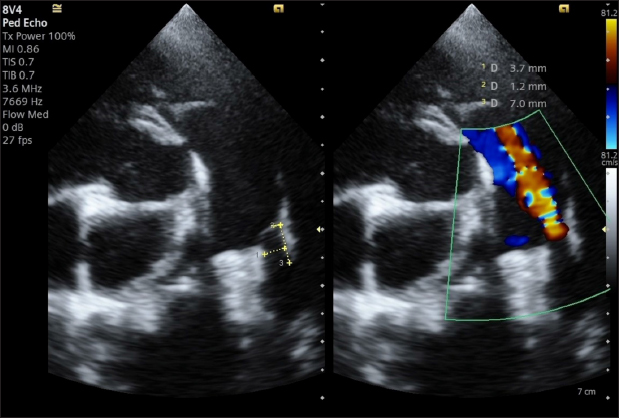

A transthoracic echocardiogram (TTE) (Siemens Acuson Juniper, Probe: 8V4, Siemens Healthcare, Erlangen, Germany) revealed mild left atrial and left ventricular dilation: Left atrium/aorta ratio: 1.8 ( reference value < 1.6), normalized to body weight), left ventricular internal diastolic diameter: 1.98 (reference value: ≤ 1.7), and left ventricle apical four-chamber view end-diastolic volume (Simpson biplane method): 23.6 mL (reference value < 20.1 mL), (Wess et al. 2021). It also revealed a small PDA, with approximate MDD and ampulla diameters of 1.2 mm and 3.7 × 7 mm, respectively, and a length of 7 mm (Fig. 2).

Fig. 2. Transthoracic echocardiography, cranial left lateral view, optimized for PDA visualization and its measurement (A) and and left-to-right flow on CFM Doppler (Dual-mode).

The dog was discharged, and a check-up was scheduled for 30 days. The 1-month TTE echocardiographic examination confirmed complete occlusion of the PDA, without residual shunting on Color Flow Mapping (CFM), correct positioning of the device, with complete reverse remodeling of the cardiac chambers (Fig. 8).

Fig. 8. Dual-mode transthoracic echocardiography (left cranial parasternal view optimized for duct visualization) at 30 days after surgery. The device (yellow square) is correctly positioned, and no evidence of residual shunt or pulmonary arterial obstruction is present on CFM Doppler.